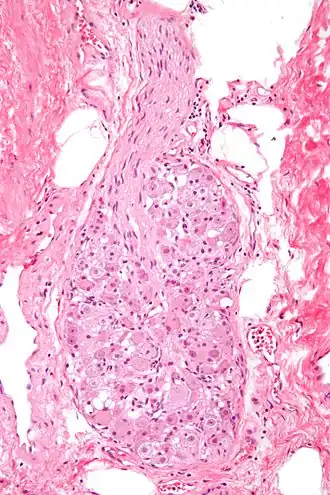

Micrograph of a ganglion. H&E stain. | |

A ganglion (pl.: ganglia) is a group of neuron cell bodies in the peripheral nervous system. In the somatic nervous system, this includes dorsal root ganglia and trigeminal ganglia among a few others. In the autonomic nervous system, there are both sympathetic and parasympathetic ganglia which contain the cell bodies of postganglionic sympathetic and parasympathetic neurons respectively.

Ganglia are primarily made up of somata and dendritic structures, which are bundled or connected. Ganglia often interconnect with other ganglia to form a complex system of ganglia known as a plexus. Ganglia provide relay points and intermediary connections between different neurological structures in the body, such as the peripheral and central nervous systems.